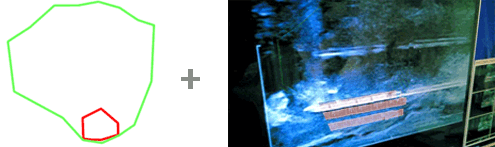

Vorbereitung zur Überlagerung des mpMRT Bildes mit dem Ultraschallbild

Computer­gestützte Über­lagerung/Fusio­nierung von Ultra­schall- und MRT-Bild

Fusionsbiopsie - Überlagerung/Fusionierung von Ultraschall- und MRT-Bild